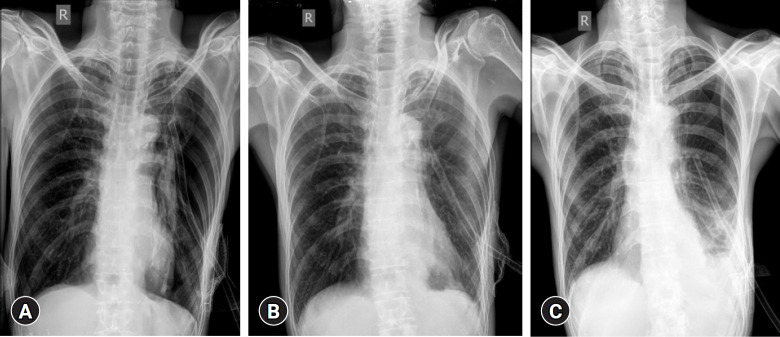

Serratia marcescens is an opportunistic gram-negative pathogen that causes pneumonia, bloodstream infections, and urinary tract infections, particularly in individuals who are immunocompromised. Although commonly associated with pulmonary infections, its involvement in pneumothorax-related infections is exceedingly rare. Secondary spontaneous pneumothorax (SSP) is a life-threatening condition that can complicate underlying lung diseases, such as chronic obstructive pulmonary disease (COPD). This case report describes a rare presentation of S. marcescens infection in a patient with SSP complicated by a bronchopleural fistula. A 64-year-old male with a history of COPD, chronic smoking, and alcohol use presented with progressive dyspnea, cough, and left-sided chest pain. Clinical evaluation revealed tachypnea, tracheal deviation, and reduced breath sounds in the left lung. Laboratory investigations revealed leukocytosis with marked neutrophilia and an elevated erythrocyte sedimentation rate. Chest imaging confirmed pneumothorax, necessitating intercostal drain (ICD) placement. Pleural fluid cultures identified multidrug-resistant S. marcescens, prompting antibiotic escalation to intravenous meropenem and oral faropenem. Despite prolonged antimicrobial therapy and ICD placement, persistent pneumothorax with a bronchopleural fistula was noted. Bronchoscopy with Fogarty balloon placement and cyanoacrylate closure was performed. However, owing to financial constraints, the patient declined follow-up cultures and high-resolution computed tomography imaging, and was discharged with an ICD in situ. This case underscores the need for heightened clinical awareness of S. marcescens in pneumothorax-associated infections. Early microbiological identification and targeted therapy are crucial for the management of rare yet challenging presentations, particularly in resource-limited settings.